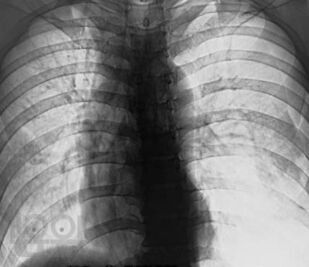

В книге изложены особенности клинической и рентгенологической диагностики повреждений и ранних осложнений закрытых травм грудной клетки. Проведен анализ объективных причин, затрудняющих основные и дополнительные методы исследования. На 240 рентгенограммах показаны признаки трудновыявляемых повреждений и осложнений травм грудной клетки, в частности пневмоторакса, гемоторакса, ателектаза, разрыва диафрагмы. Впервые отмечается клиническая значимость напряжения в малом пневмотораксе при политравме. Приведены сравнительная характеристика и алгоритм дифференциальной диагностики острых диффузных поражений легких при травме. Описан опыт выявления и решения проблемы нефункционирующего дренажа плевральной полости. Издание предназначено для хирургов, торакальных хирургов, травматологов, реаниматологов, оказывающих помощь больным с политравмой.